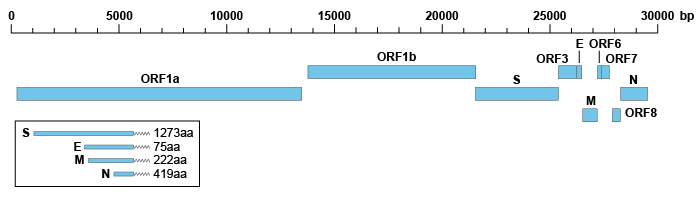

SARS-CoV-2 是一种约 30kb 的阳性单链 RNA 病毒,其基因组组成与 SARS-CoV 相似,两者都是由两个主要的开放阅读框(ORF)和几个较小的下游 ORF 组成。

两个主要的 ORF(ORF1a 和 ORF1b)编码两个多肽,被病毒编码的蛋白酶切割后产生非结构蛋白(nsps)。ORF1a 编码 440-500 kDa 多肽(pp1a),该多肽经过酶处理裂解成 11 个 nsps。ORF1b 编码 740-810 kDa 的较大多肽(pp1ab),该多肽被切割为 16 个 nsps。

在 SARS-CoV-2 中已鉴定出四种主要的结构蛋白,包括刺突蛋白、核衣壳蛋白、膜蛋白和包膜蛋白,与 SARS-CoV 具有显著的同源性。这四个结构蛋白由 ORF2-10 编码,是病毒形成外壳和基因组衣壳化所必需的。与非结构蛋白相比,结构蛋白能引发更高水平的体液免疫和细胞免疫反应。